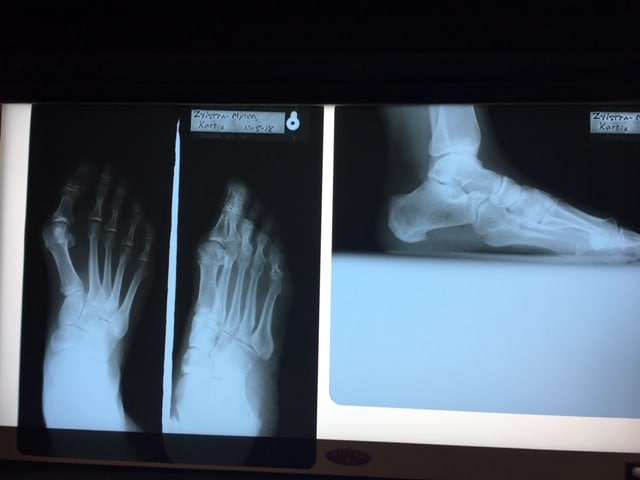

The first photo shows my sad and crooked foot BEFORE. Below is my corrected foot with a screw through the top that may or may not set off the security alarms when I get to those metal detectors. We will see.